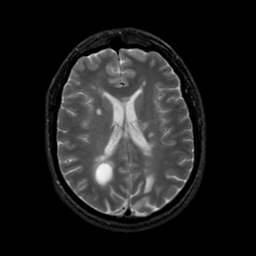

MR Study #22, December 1, 1991 -- Slice #30